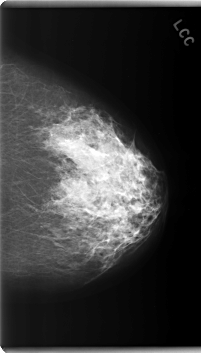

C_0208_1.LEFT_CC

LEFT_CC LINES 5992 PIXELS_PER_LINE 3416 BITS_PER_PIXEL 12 RESOLUTION 50 NON_OVERLAY